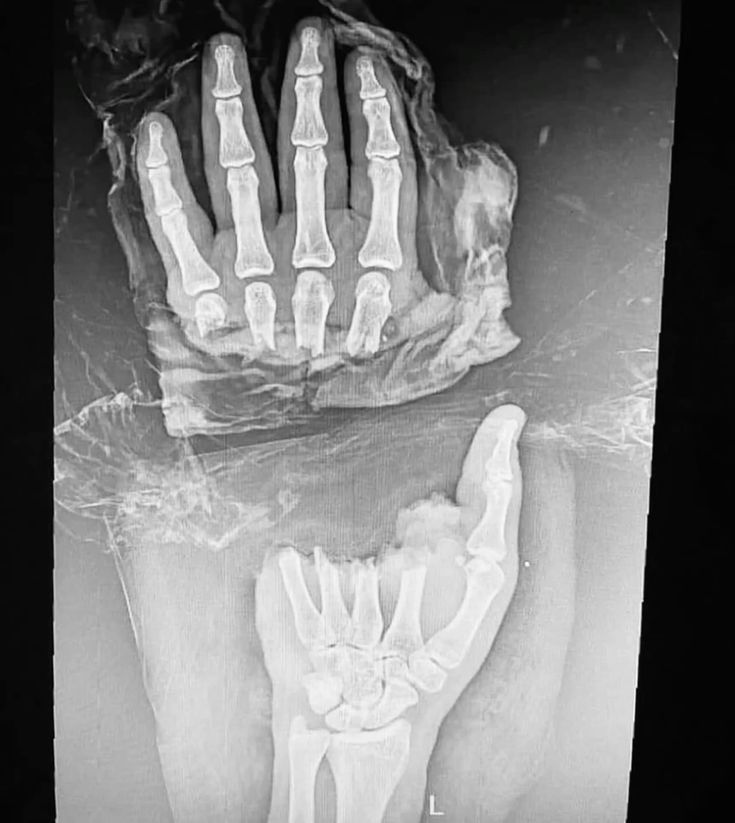

Mon Pitbull était un peu énervé aujourd’hui

Je suis à l’hôpital à cause de lui mais rien de grave je l’aime tellement

Oui il a tellement d’énergie quand il joue